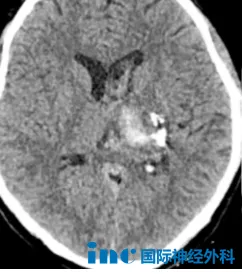

28岁男性患者李先生已与疾病抗争数月。在接受动静脉畸形栓塞术和伽马刀放射治疗后,近期复查发现"左侧丘脑脑出血伴脑室内积血"。目前仍存在右侧肢体麻木、视野缺损等症状。在伽马刀疗效尚未完全显现的阶段,患者急需明确保守治疗可行性及是否需要再次手术干预。

巴特朗菲教授详细评估后指出,基于患者目前病情稳定,前期治疗已对动静脉畸形产生控制作用,整体病情处于可控状态。因此现阶段不建议再次进行介入手术。教授分析认为,此时若行手术,患者获益有限但需承担相应手术风险,风险效益比不佳。教授建议患者保持血压稳定,维持适度日常生活,并继续观察病情变化。若病情持续稳定无新发症状,则说明当前治疗方案适宜,无需急于追加干预。